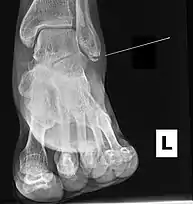

Ankle radiographs are used to detect widening of the tibiofibular syndesmosis or medial clear space. The medial clear space is the area between the talus of the ankle and the medial malleolus. Damage to the deltoid ligament and syndesmotic ligaments result in mortise instability, causing the talus to laterally shift and widen the medial clear space.[4][12] A clinical study, conducted in 2006 and published in the Journal of Bone and Joint Surgery, found that the medial clear space size of a normal ankle and an injured ankle measured at 4 millimetres and 5.4 millimetres in length respectively.[11] To confirm diagnosis, full-leg radiographs are used to inspect for fractures of the proximal fibula and widening of the interosseous clear space (or tibiofibular clear space). The interosseous clear space is the area between the medial side of the fibula and lateral side of the tibia. A peer-reviewed study, published in Injury in 2004, found that an interosseous clear space greater than 10 millimetres indicates diastasis of the syndesmotic ligaments.[4]